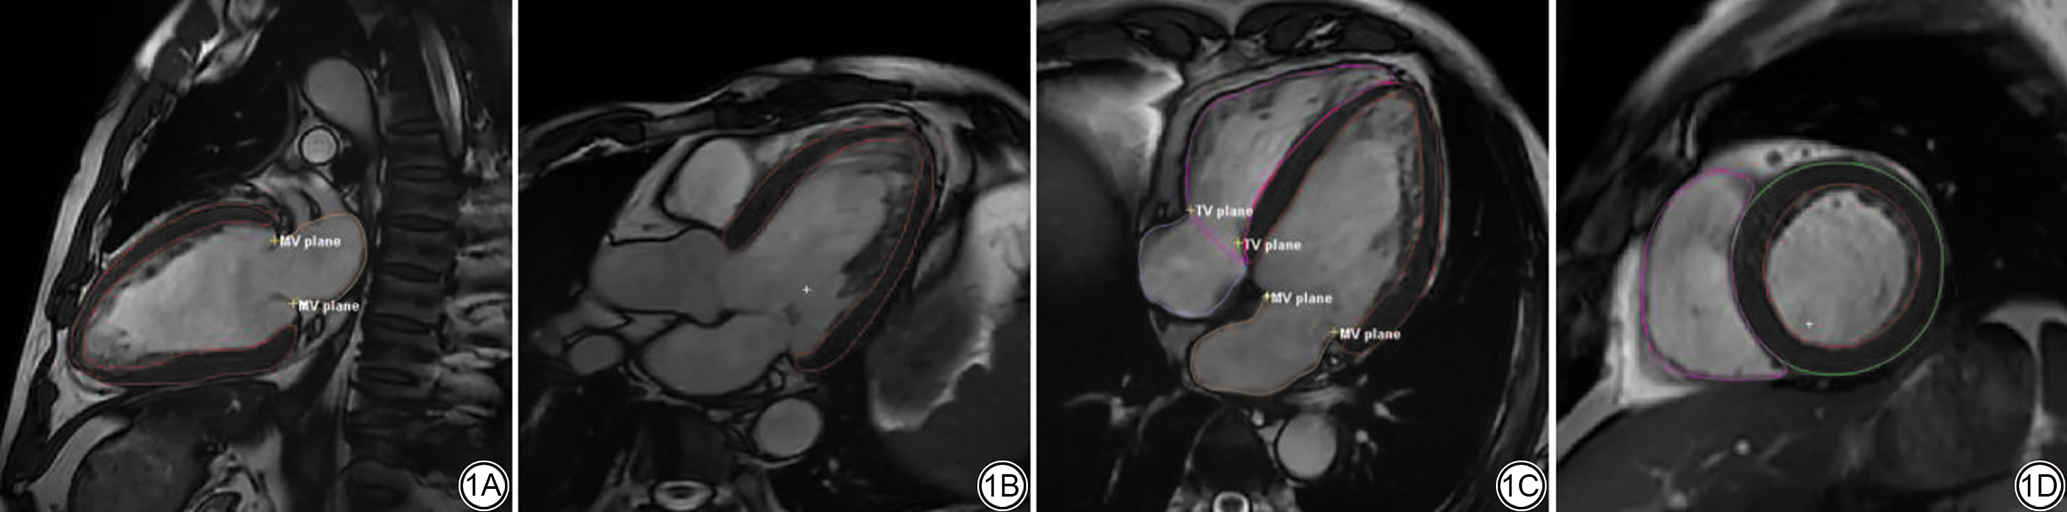

1.3 心脏功能和特征跟踪分析

所有CMR研究均使用专用软件Segment Medviso version 3.3 RX及uMR670机器自带心脏后处理分析软件进行离线分析。通过心肌特征跟踪测量整个心动周期的心肌应变,在舒张末期短轴、包含心尖的3腔长轴层面、包含心尖的2腔长轴层面和包含心尖的4腔长轴层面图像中手动追踪心内膜和心外膜边界。对各应变参数(心室周向应变、径向应变和纵向应变、心房储存应变、导管应变、泵应变)的峰值测量值进行分析。为计算双心室功能参数,包括RV/LV收缩末期容积指数(end-systolic volume index, ESVI)、RV/LV舒张末期容积指数(end-diastolic volume index, EDVI)、左室心肌质量指数(left ventricular myocardial mass index, LVMI)、左心室重塑指数(left ventricular remodeling index, LVRI)和RV/LV EF,在收缩末期和舒张末期的连续短轴图像中追踪左心室外膜和内膜边界/右心室内膜边界。RV/LV EDVI、RV/LV ESVI和LVMI通过LV舒张末期容积(end-diastolic volume, EDV)、LV收缩末期容积(end-systolic volume, ESV)、左室心肌质量(left ventricular myocardial mass, LVM)除以体表面积(body surface area, BSA)得出。LVRI计算为LVM除以LV EDV。为分析双心室及双心房特征跟踪参数,以舒张末期设置为参考点,跟踪额外的左心室四腔、三腔和两腔纵视图和右心室、双心房四腔纵视图。3D LV应变参数[左心室全局纵向应变(global longitudinal peak strain in the left ventricle, LV GLS)、左心室全局径向应变(global radial strain of the left ventricle, LV GRS)、左心室全局周向应变(global circumferential strain of the left ventricle, LV GCS)和各方向左心室收缩/舒张期峰值应变率(peak systolic/diastolic strain rate of the left ventricle, LV PSSR/LV PDSR)],2D RV应变参数[右心室全局纵向应变(global longitudinal peak strain in the right ventricle, RV GLS)、右心室全局周向应变(global circumferential strain of the right ventricle, RV GCS],2D左心房/右心房(left atrium/right atrium, LA/RA)应变参数[LA/RA储存应变(store strain, ξs)、LA/RA导管应变(extrusion strain, ξe)、LA/RA泵应变(activity strain, ξa)]在执行这些轮廓跟踪后自动生成(图1)。

图1  2型糖尿病组心内膜和心外膜边界追踪视图。1A:左心室两腔纵视图;1B:左心室三腔纵视图;1C:双心室、双心房四腔纵视图;1D:双心室舒张末期短轴视图。

Fig. 1  Tracking view of endocardial and epicardial boundaries in the type 2 diabetes mellitus. 1A: Left ventricular two-chamber longitudinal view; 1B: Left ventricular three-chamber longitudinal view; 1C: Biventricular and biatrial four-chamber longitudinal view; 1D: Biventricular end-diastolic short-axis view.